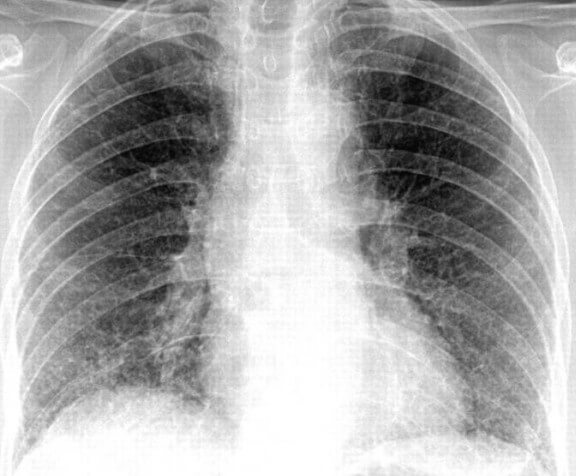

Чтобы правильно поставить диагноз, необходимо сдать кровь, мокроту для лабораторных исследований, и сделать рентген грудной клетки. Если диагноз поставлен правильно, врач назначает лечение антибиотиками. При пневмонии это самое верное средство лечения. Антибиотики при пневмонии помогают устранить очаг воспаления.Применение противомикробных препаратов необходимо, чтобы не допустить развитие болезнетворных организмов, бактерий, палочек, вирусов и свести к минимуму риск развития осложнений. Если своевременно не начать лечение, можно упустить время. Из-за этого последующее лечение может продлиться очень долго, а в некоторых случаях промедление приводит к летальному исходу.

Для лечения воспаления легких необходимо принимать антибиотики не меньше семи дней. После этого делают контрольный рентген грудной клетки, чтобы исключить наличие очага инфекции в легких. Если он будет обнаружен, повторяют курс лечения, но уже другим антибактериальным препаратом. В некоторых случаях возможна консультация у фтизиатра.Воспаление легких обязательно должно лечиться в стационаре. Самостоятельно, и часто неправильно подобранные антибиотики во многих случаях вызывают побочные эффекты, состояние больного может ухудшиться, повышается риск развития осложнений и ухудшается прогноз вылечивания пневмонии.